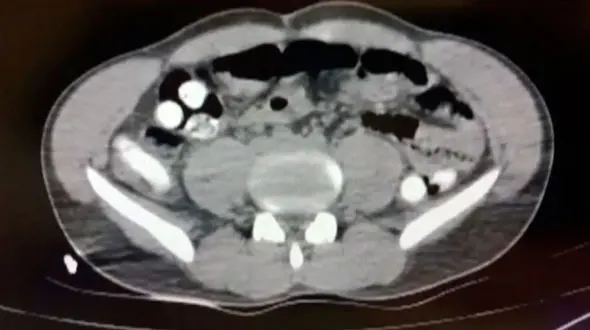

تصویری از معده فردی که ۱۰۲ کپسول حاوی تریاک را قورت داده بود.

حوادث رکنا:فرمانده انتظامی گناباد گفت: یک زن میانسال که به صورت انباری اقدام به حمل و جابجایی مواد مخدر میکرد بر اثر بازشدن این مواد در معدهاش جان خود را از دست داد.

حوادث رکنا: فرمانده انتظامی بردسکن از کشف یک کیلو و 400 گرم تریاک از معده دو قاچاقچی در این شهرستان خبر داد.